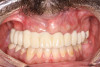

Fig 7. Maxillary provisional prosthesis seated on implants, on the day of surgery.

Figure 7

Fig 8. Implants and provisional maxillary prosthesis in place, the same day as surgery.

Figure 8

The completed provisional prosthesis was then screwed onto the multi-unit abutments with titanium screws and torqued to 20 Ncm. Screw-access holes were filled, and no occlusal adjustment was necessary. The fit of the prosthesis was precise and stable, and the patient's phonetics were ideal. The patient was overwhelmed by the significant esthetic improvement with this set of teeth in place (Figure 6 through Figure 8).